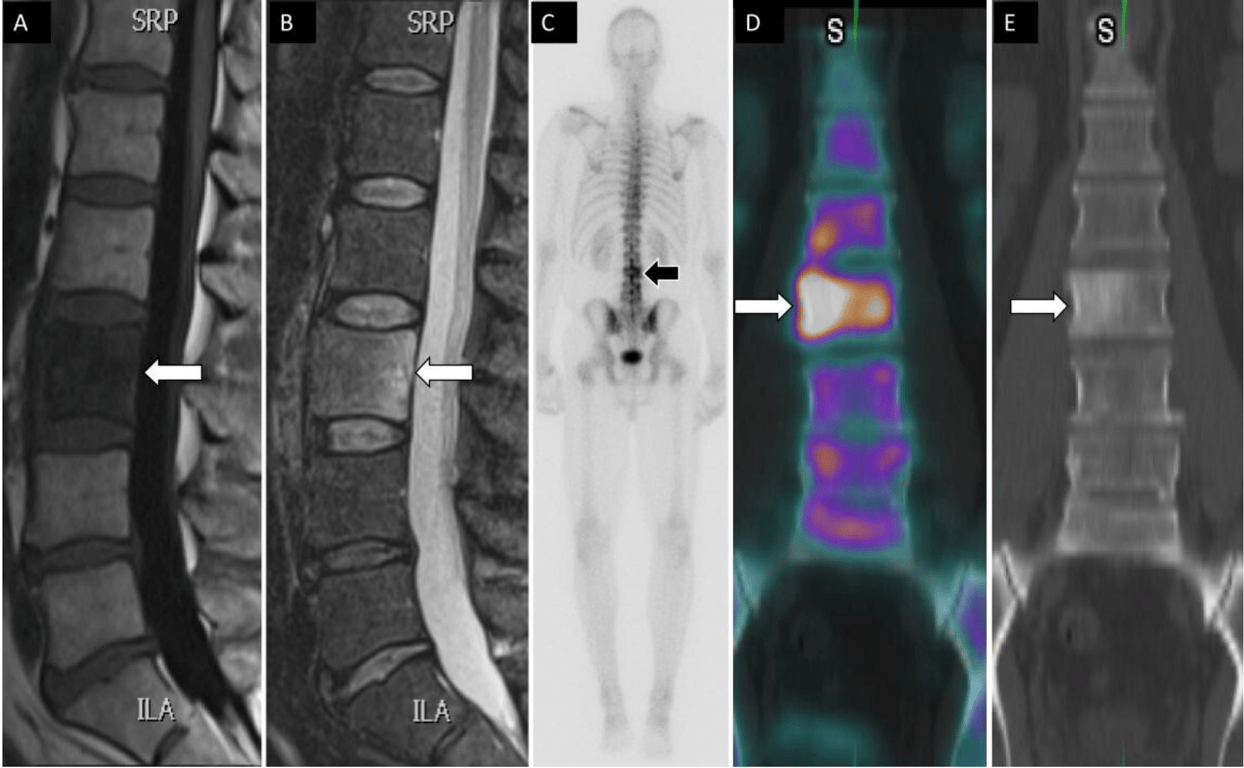

A 49-year-old man had a history of tonsillar squamous cell carcinoma and low back pain. Sagittal T1 (A) and STIR (B) magnetic resonance images show low T1 and high T2 signal changes within the L3 vertebral body (arrows). Posterior planar 99mTc-MDP bone scan image (C) shows increased osteoblastic activity at L3 vertebral body. Coronal fused single photon emission computed tomography with computed tomography image (D) demonstrates an osteoblastic lesion within the right L3 vertebral body with associated sclerotic changes on computed tomography (E) compatible with metastatic bone lesion.